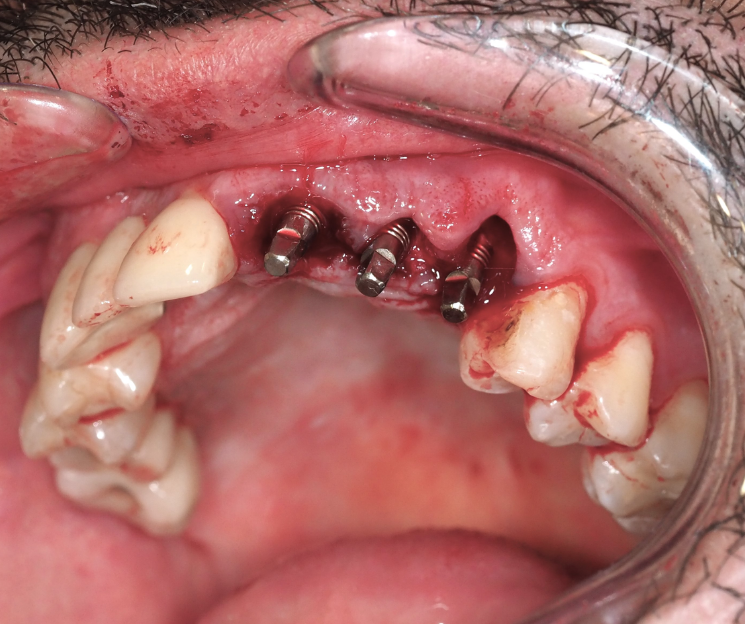

Extracción de piezas 21, 22 y 23 con infección activa

Paciente con infecciones de origen dental que comprometían severamente el hueso alveolar en la zona anterior superior. Se realizó la extracción de los dientes 21, 22 y 23, y se optó por una rehabilitación inmediata mediante implantes córticobasales.

Estrategia protésica e implantes utilizados:

- 1 implante córticobasal compresivo

- 2 implantes córticobasales rectos y finos

Esta combinación permitió anclar los implantes en hueso cortical, que mantiene su estabilidad incluso en presencia de procesos infecciosos en el hueso alveolar. El resultado: rehabilitación funcional y estética el mismo día de la cirugía.